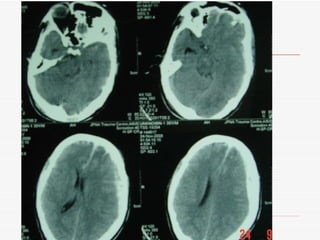

Decompressive craniectomy is used at JPNATC to treat severe traumatic brain injuries. Between January 2008 and November 2008, 24.1% of patients with severe head injuries underwent decompressive craniectomy. The indications for decompressive craniectomy at JPNATC include severe head injury with acute subdural hematoma, midline shift, and mass effect; intracerebral contusions with mass effect and midline shift; and diffuse axonal injury with effaced cisterns and intracranial pressure above 20 despite maximum medical therapy.